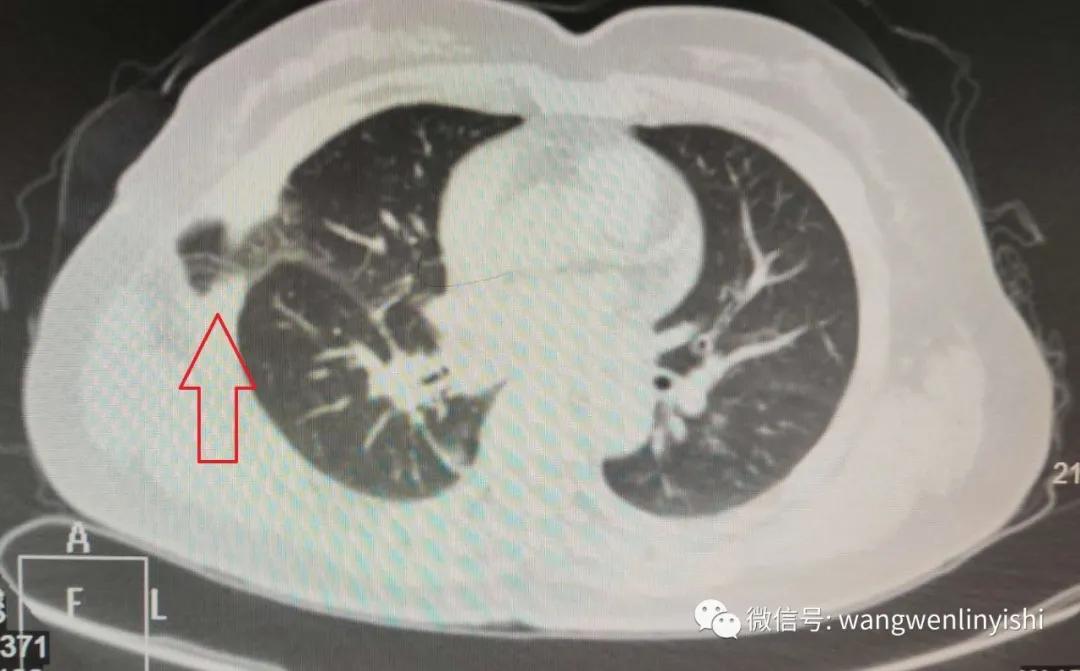

患者为中年女性,因肺部小结节在某院接受胸腔镜手术,术后患者出现剧烈咳嗽,经对症处理效果不佳入我院。行CT检查,发现右侧手术切口处有明确胸壁缺损,肺组织嵌入缺损,形成切口疝。患者诊断明确,为胸部手术后的胸壁缺损,切口疝。考虑到缺损较大,我们采用保守方法做处理。经一周治疗,症状消失。再次复查CT,肺组织回复胸腔,但胸壁缺损尚存。考虑到缺损较小,不做特殊处理,病人出院。

(胸壁缺损)